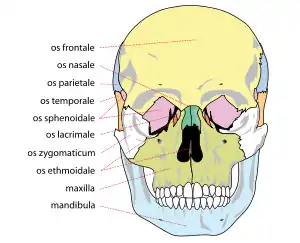

Kraniet set forfra |

Ansigtsskelettet

Der findes følgende knogler i ansigtsskelettet:

- Overkæbeben (1 par, maxilla)

- Underkæbeben (mandibula)

- Tungeben (Os hyoideum) – (halsknogle.)

- Ganeben (1 par, Os palatinum)

- Næseben (1 par, Os nasale)

- Tåreben (1 par, Os lacrimale)

- Plovskærben (Vomer)

- Kindben (1 par, Os zygomaticum)

- Det nedre muslingeben (1 par, Concha nasalis inferior)

Ansigtsskelettet er den del af kraniet, der kan ses forfra, og består derfor udover ovennævnte knogler også af pandebenet (den del, der kaldes squama frontalis)

Menneskets kranium (forfra).

Menneskets kranium (forfra). Menneskets kranium (fra siden).